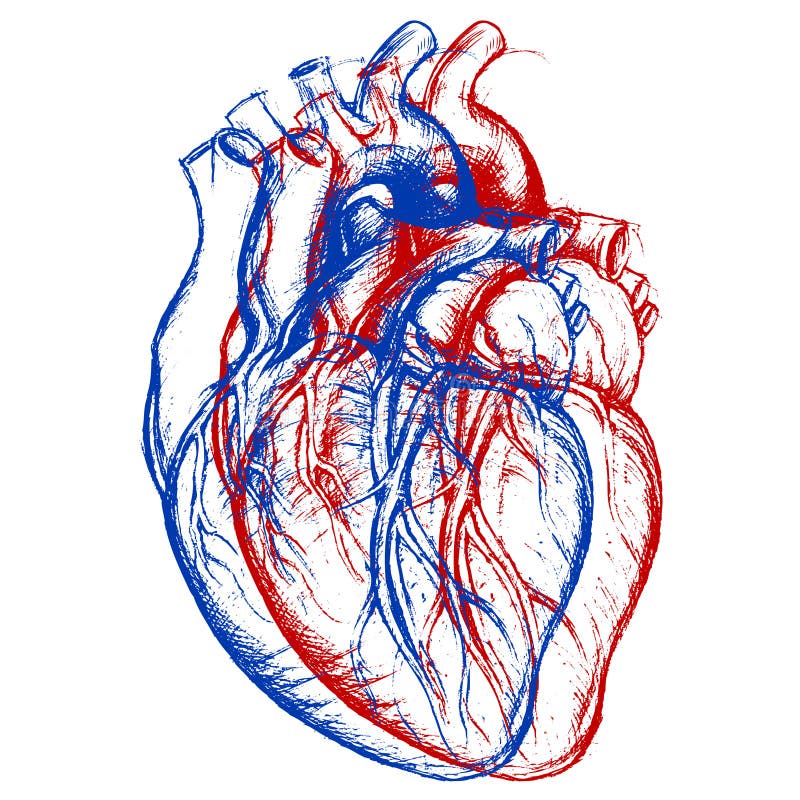

Human Heart 3D stock vector. Image of doodle, organ, conceptual - 43760249

Pin by Kelly Kener on Art (With images) | Heart pencil drawing, Human heart drawing, Drawings

Pin by Kelly Kener on Art (With images) | Heart pencil drawing, Human heart drawing, Drawings  Human Heart Drawing Outline at GetDrawings | Free download

Realistic detailed 3d human anatomy heart Vector Image  3D human heart model - TurboSquid 1149348